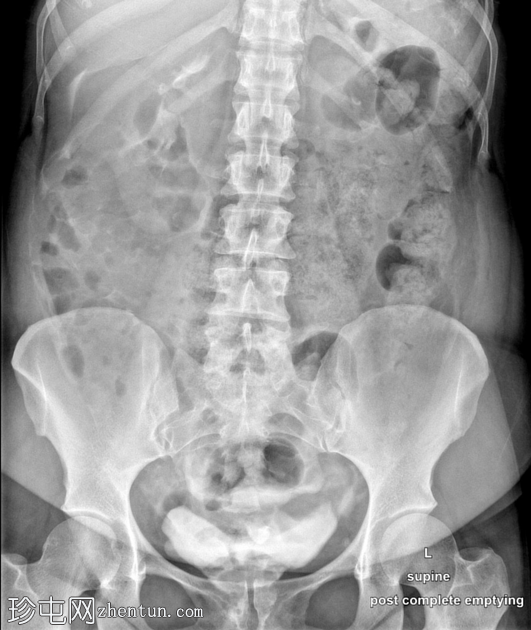

正位

经Foley导尿管向膀胱内注入约700毫升造影剂。

子宫内可见造影剂积聚,膀胱上表面与子宫之间存在异常瘘管连接。同时可见造影剂从输卵管溢入腹腔。

影像

学表现符合膀胱子宫瘘。